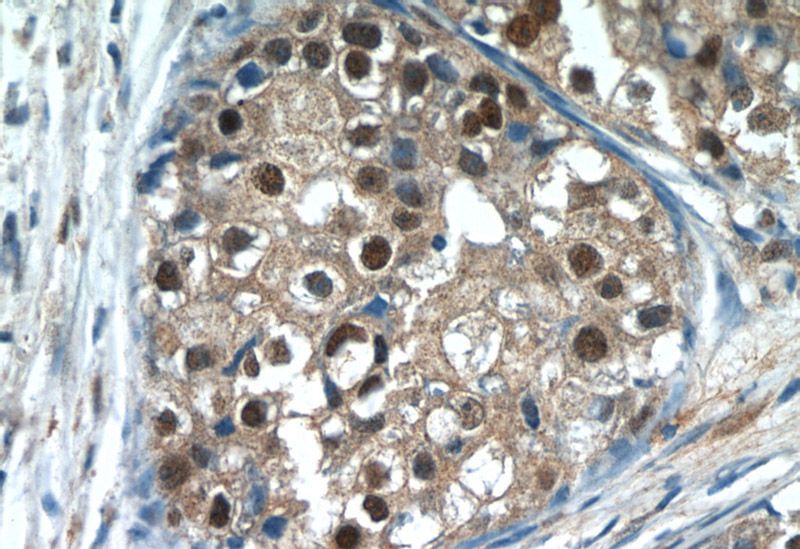

Immunohistochemistry of paraffin-embedded human breast cancer tissue slide using Catalog No:112567(MDC1 Antibody) at dilution of 1:50 (under 40x lens)